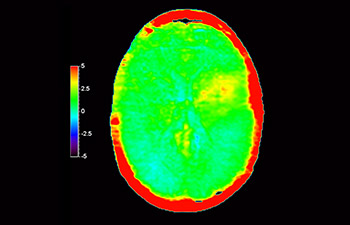

Neurologische Leiden stellen eine schwere Belastung dar. Philips hat es sich zum Ziel gesetzt, hochwertigste Neuro-Bildgebung zu ermöglichen – für eindeutige Diagnosen und eine schnelle Therapie. Wenngleich die MRT heutzutage den Goldstandard in der neuroradiologischen onkologischen Bildgebung darstellt, kann die Genauigkeit beim Tumor-Grading und den Nachsorgeuntersuchungen noch weiter verbessert werden. 3D APT (Amide Proton Transfer) ist eine einzigartige, kontrastmittelfreie Methode zur MR-Tomographie des Gehirns, die den Bedarf nach einer sichereren Diagnose in der Neuroonkologie erfüllt. 3D APT nutzt das Vorhandensein von endogenen zellulären Proteinen zur Erzeugung eines MR-Signals, das direkt mit der Zellproliferation, einem Marker für Tumoraktivität, korreliert. 3D APT kann geschulte medizinische Fachkräfte dabei unterstützen, gering differenzierte von hochdifferenzierten Gliomen und Tumorverhalten von Behandlungseffekt zu unterscheiden1.